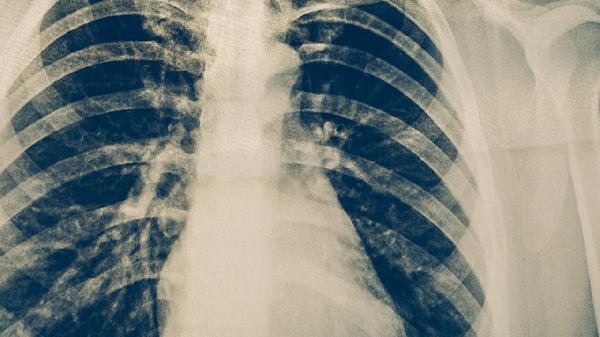

肺癌淋巴结转移的途径主要有直接浸润、淋巴管扩散、血行转移、种植转移和跳跃性转移。肺癌淋巴结转移通常与肿瘤细胞侵袭淋巴系统有关,可能伴随淋巴结肿大、疼痛等症状。

肺癌细胞可直接向周围淋巴结浸润,常见于肺门淋巴结和纵隔淋巴结。肿瘤细胞突破原发灶边界后,沿组织间隙向邻近淋巴结生长。这种情况多见于中央型肺癌,可能伴随咳嗽加重或咯血。治疗需根据肿瘤分期选择手术切除或放化疗。

肿瘤细胞侵入淋巴管后,可随淋巴液流动转移至区域淋巴结。右肺上叶癌多转移至右气管旁淋巴结,左肺上叶癌易转移至主动脉弓旁淋巴结。淋巴管扩散早期可能无明显症状,晚期可出现淋巴回流受阻导致的上肢水肿。诊断依赖PET-CT检查。